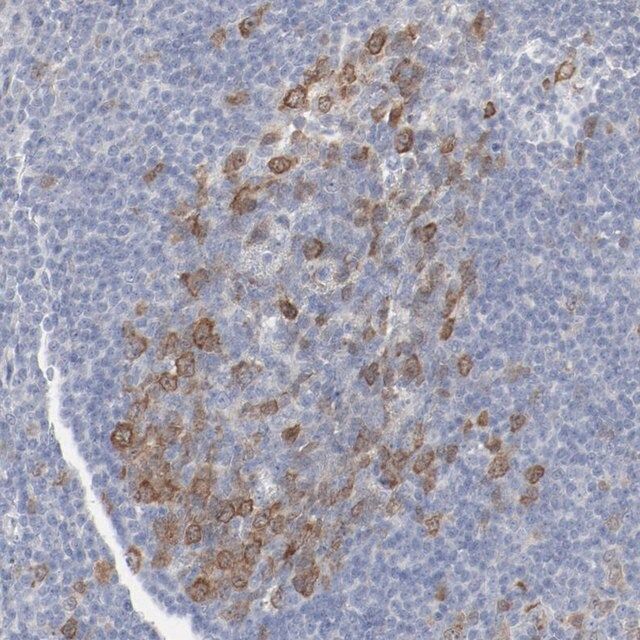

Anti-CDK1 antibody produced in rabbit, a Prestige Antibody, is developed and validated by the Human Protein Atlas (HPA) project (www.proteinatlas.org). Each antibody is tested by immunohistochemistry against hundreds of normal and disease tissues. These images can be viewed on the Human Protein Atlas (HPA) site by clicking on the Image Gallery link. The antibodies are also tested using immunofluorescence and western blotting. To view these protocols and other useful information about Prestige Antibodies and the HPA, visit sigma.com/prestige.

- IHC tissue array of 44 normal human tissues and 20 of the most common cancer type tissues.